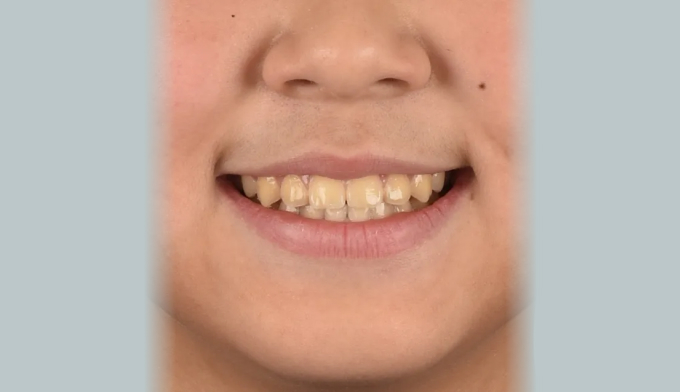

안모상으로 주걱턱 경향은 심해보이지 않고, 앞니의 약간의 반대교합만 관찰됩니다.

하지만 옆모습 엑스레이 분석시 주걱턱 수치가 높게 나와 성장교정이 필요한 케이스 입니다.

초등학교 2학년때부터 6학년때까지 진행되었습니다.